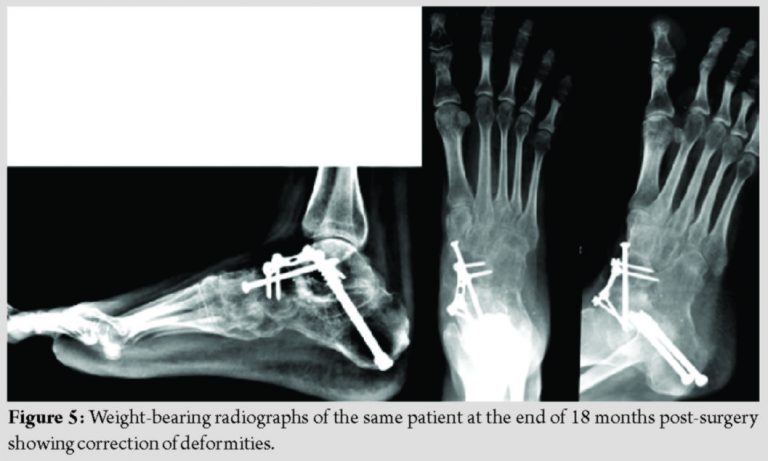

Postoperatively, she was immobilized for 4 weeks. Progressive weight-bearing with ankle range of motion physiotherapy was advised at the end of 6 weeks. The patient went back to all activities of daily living by 4 months.Her post-surgery AOFAS score was calculated as 72. At present, at 18 months post-surgery, she is asymptomatic (Fig. 4 and 5).